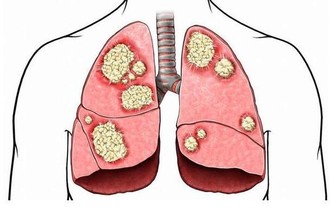

長久以往身體的狀態就有可能會受到或多或少的影響,雖然維生素是一種非常好的營養補充劑,但若是補充過量不僅不會給身體帶來益處,

03.不要盲目吃維生素,提醒:這4種維生素若過量服用,或會引起中毒